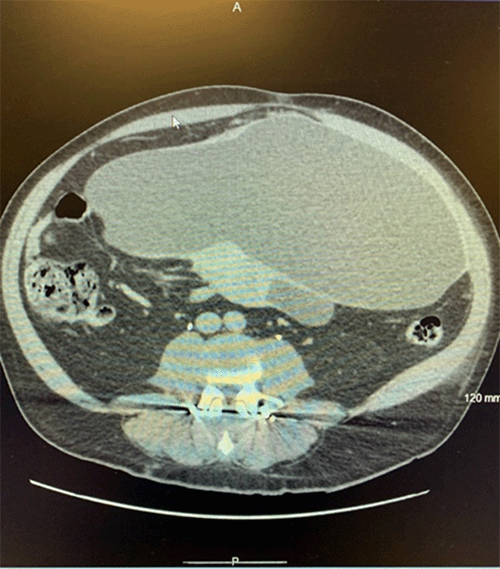

Physical examination revealed a distended abdomen with focal tenderness in the left lower quadrant and hypogastric region. A soft mass was readily palpable in this area. Abdominopelvic CT scan identified a large (30 × 14 × 17 cm) cystic mass with areas of calcification arising from either the mesentery and/or the distal small bowel (Figure 1).

Figure 1. Abdominopelvic CT Scan of Giant Cystic Mass. Published with Permission